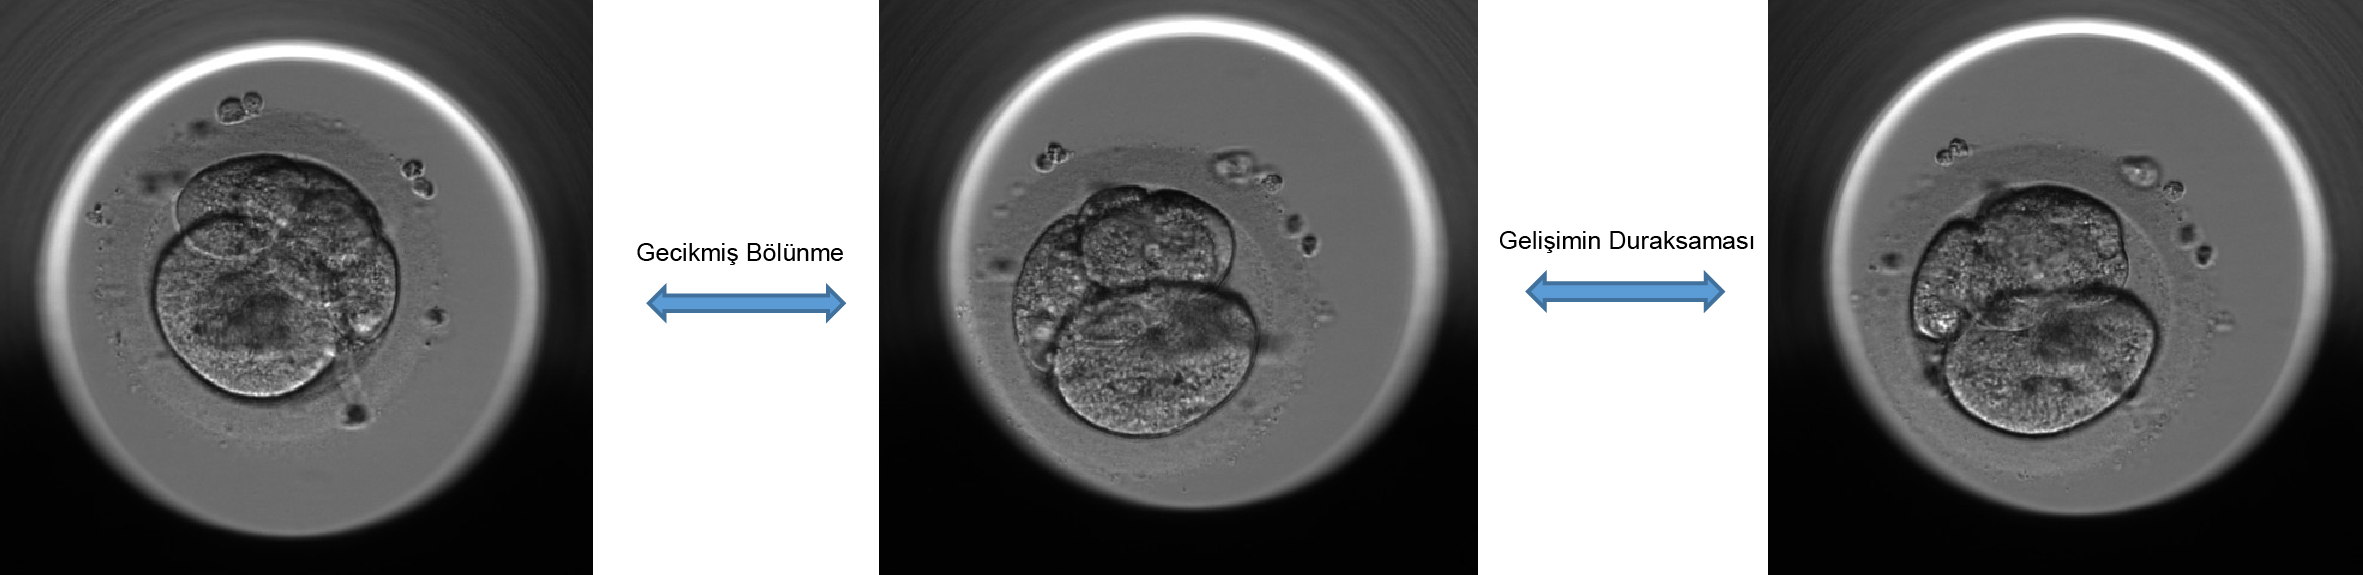

Çok hızlı veya çok yavaş bölünmeler embriyolar için zayıf gelişim potansiyelini gösterir. Çok hızlı bölünmeler, genetik materyalin yanlış ayrılmasına ve anöploidiye yol açabilirken, çok yavaş olan bölünmeler hücre döngüsünü durduran hücre döngüsünün kontrol noktalarından birini etkinleştiren DNA hasarının veya kromozomal bozuklukların bir işareti olabilir.

Sonuç olarak kesintisiz embriyo takip sistemi embriyo gelişiminde embriyoların seçim ve elenmesinde önemli katkılar sağlamaktadır. Simetrik ve senkron bölünerek gelişen embriyoların blastokist evresine ulaşma ve gebelik oluşturma potansiyelleri daha yüksek iken doğrudan bölünme ile hücre sayısının başlangıçta hızlı artması ya da ters bölünme izlenen hücrelerin tekrar geriye birleşmeleri gibi gelişimi negatif etkileyen parametreler ileri embriyo gelişiminde yavaşlamalara neden olmaktadır. Merkezimizde tutunma potansiyeli düşük olan bu embriyolar sürekli izleme cihazı ile değerlendirilerek elenirken iyi gelişen embriyolara transfer için öncelik tanınmaktadır.